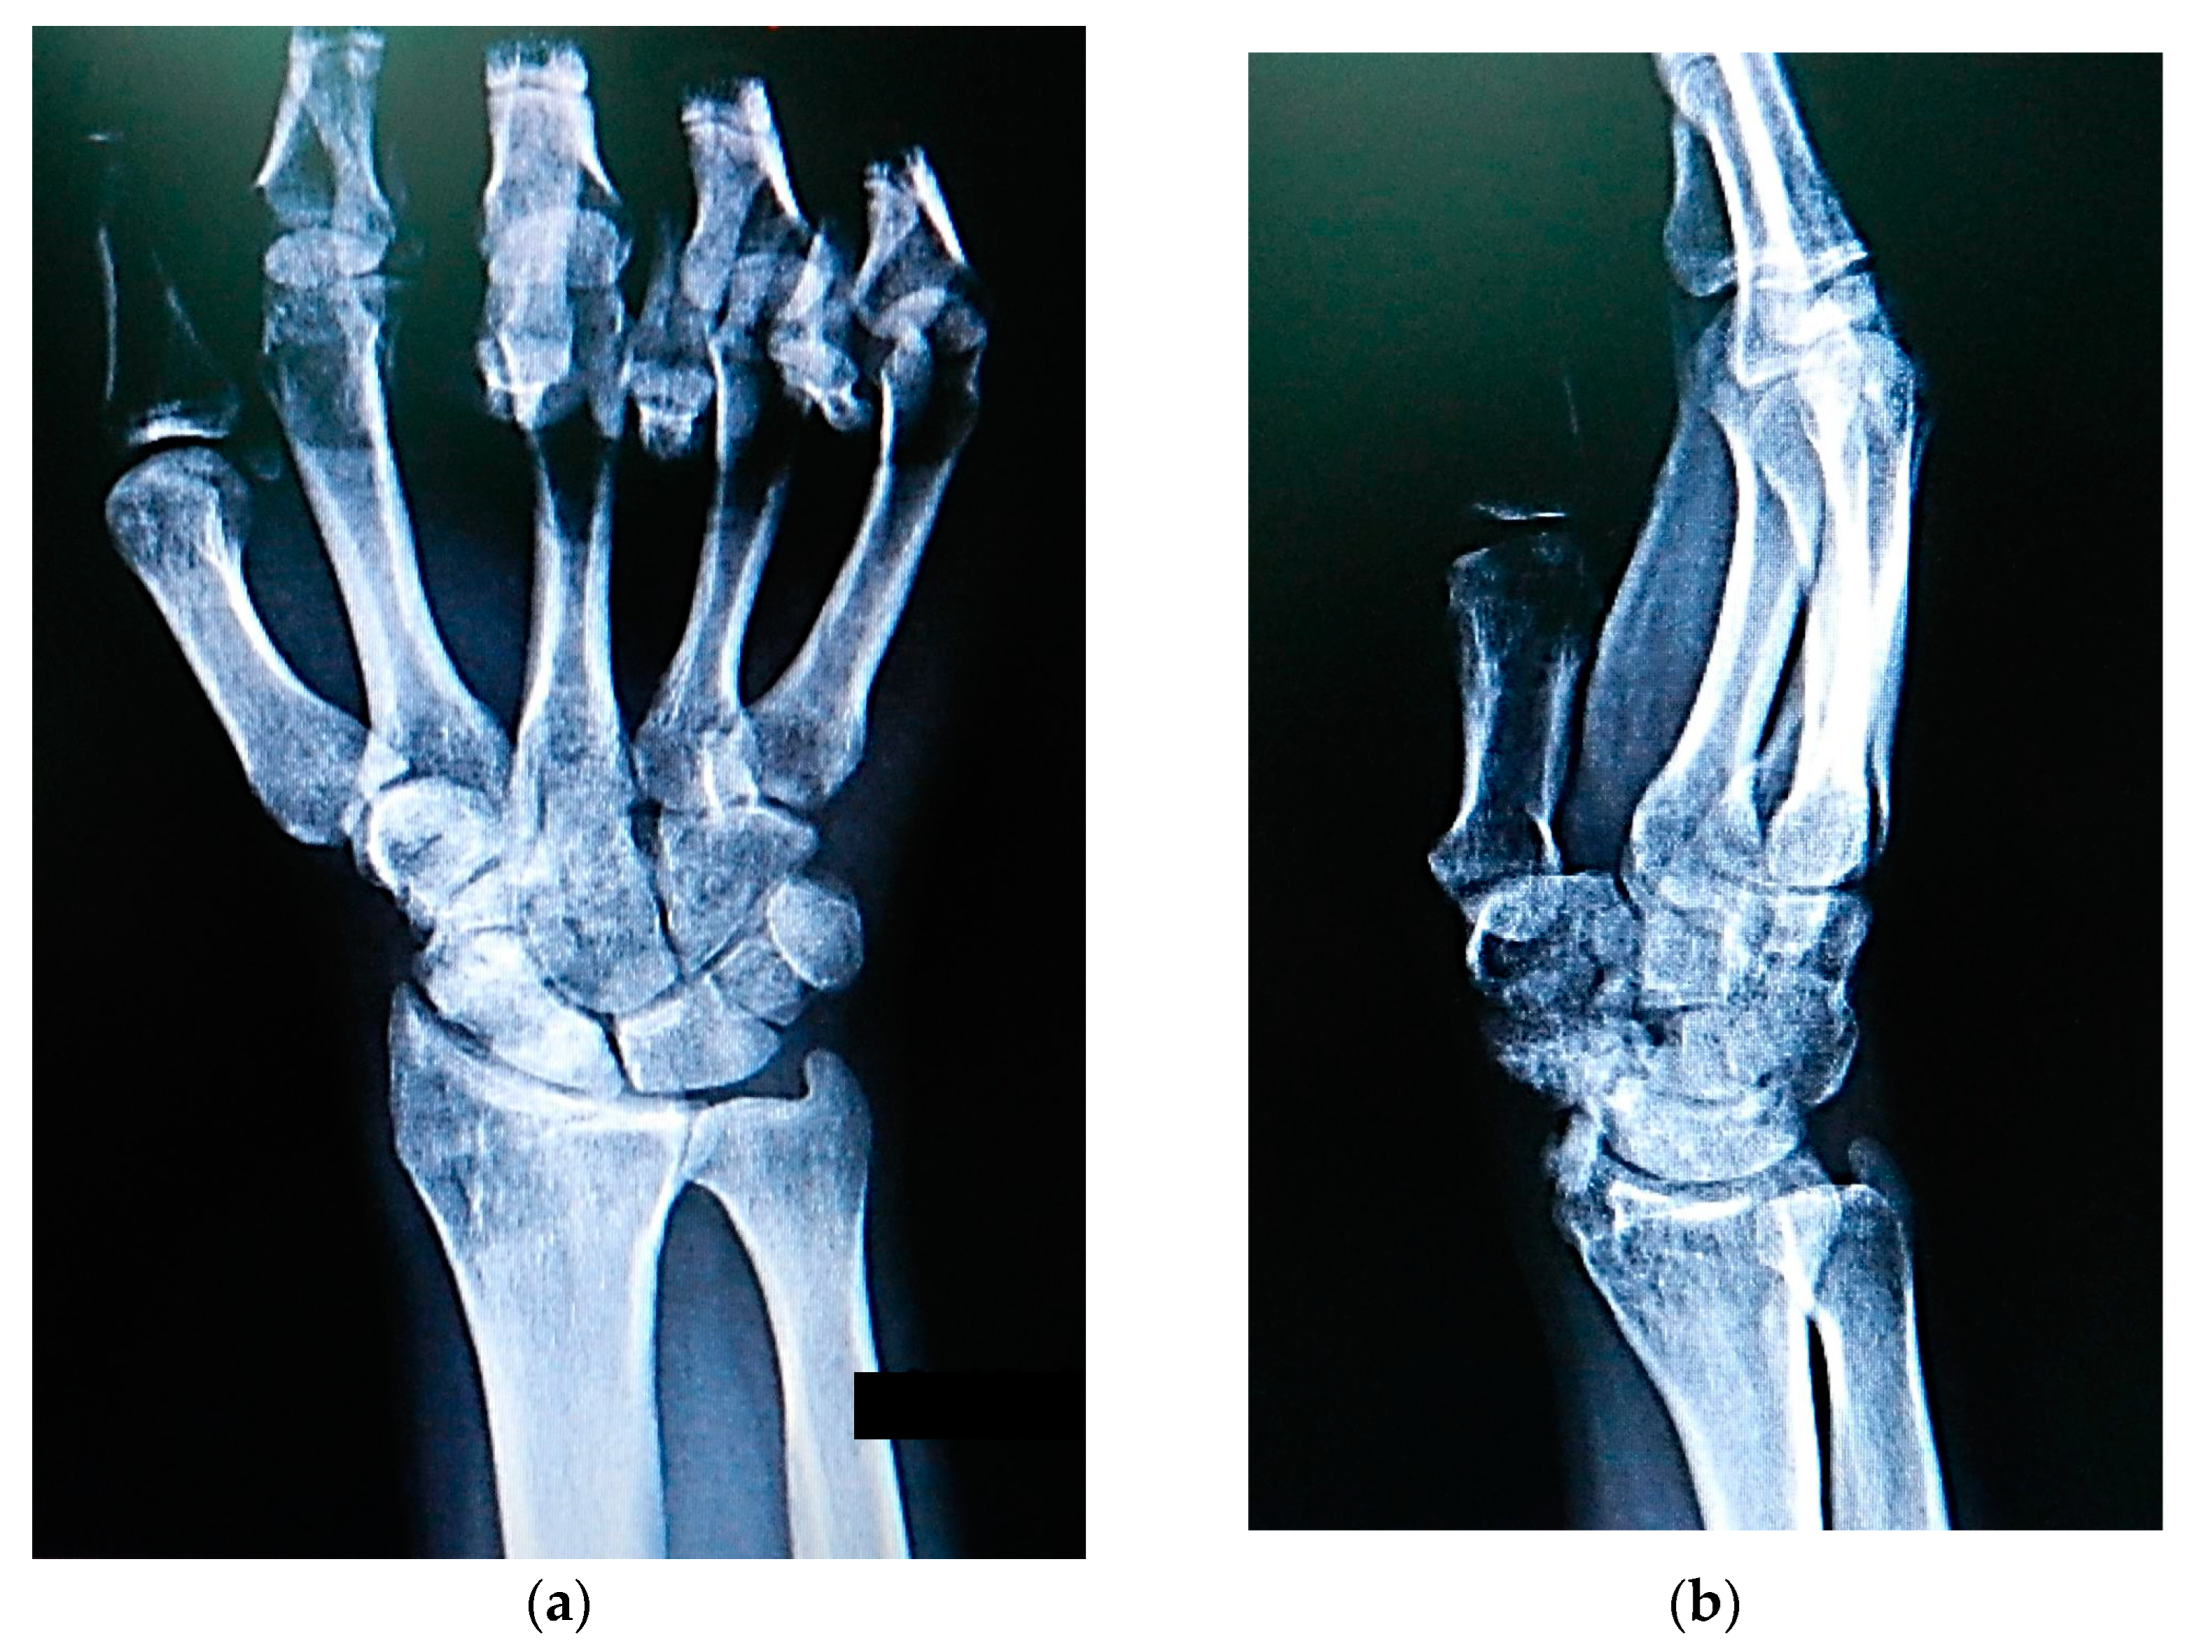

Scaphoid nonunion was defined as the absence of bony bridging the fracture for at least 6 months after the injury. The clinical diagnosis was confirmed by posteroanterior, lateral, and scaphoid radiographic views (Figure 2), whereas avascular necrosis of the scaphoid segment was diagnosed by contrast-enhanced MRI and confirmed intraoperatively by the lack of punctate bleeding at the fracture line.

Figure 2. Radiographs showing scaphoid nonunion: (a) posteroanterior; (b) lateral; and (c) scaphoid radiographic views.